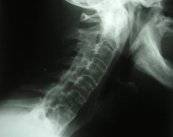

Ejercicios para tratar la Artritis Reumatoide

La Artritis Reumatoide es una patología cuyas causas no son bien conocidas. Por lo general la presentan una de cada 200 personas en la población general y con mayor frecuencia en las mujeres que van de los 40 a los 60 años de edad.